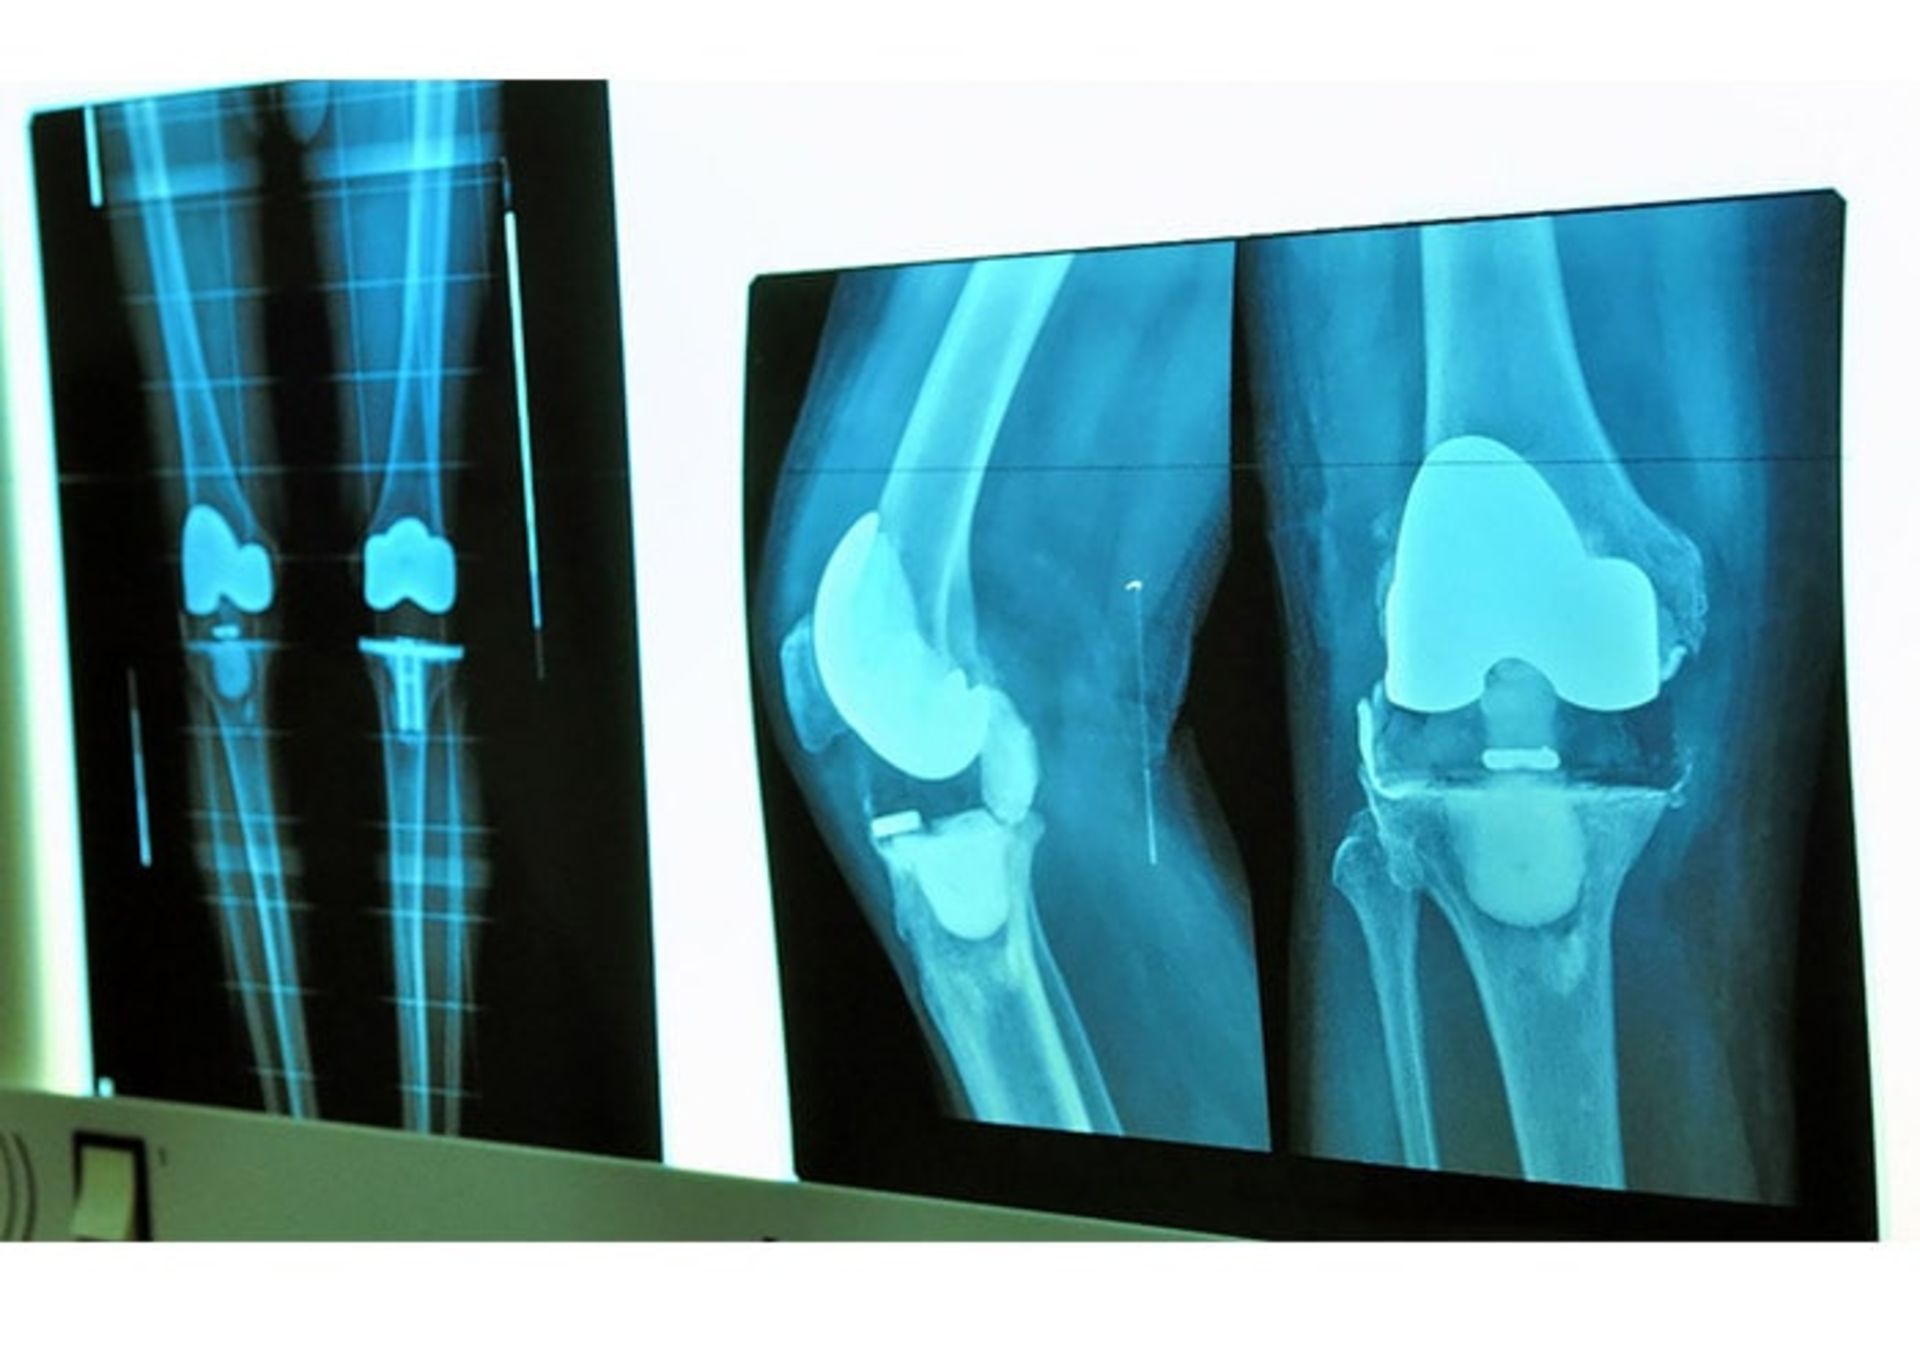

۲. اشعه‌ی ایکس: اشعه‌ی ایکس ممکن است آسیب و دیگر تغییرات مرتبط با آرتروز را نشان دهد.

عمل جراحی: جراحی مفصل می‌تواند مفصل‌های به‌شدت آسیب‌دیده‌ای مانند مفصل ران‌ها یا زانوها را ترمیم یا تعویض کند.

تعویض مفصل

تعویض مفصل گاهی تنها راه درمان آرتروز ران است